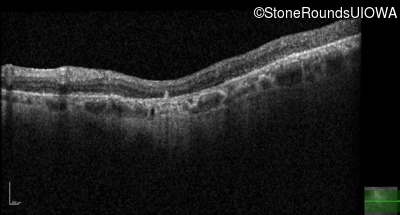

Optical Coherence Tomography - Left - 20/100

Exemplar / OCT Stack